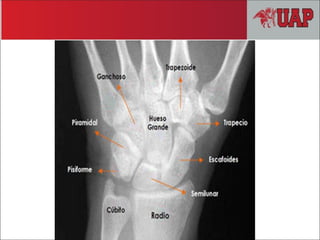

MANO

Gray – Anatomíapara estudiantes pág. 709 MANO